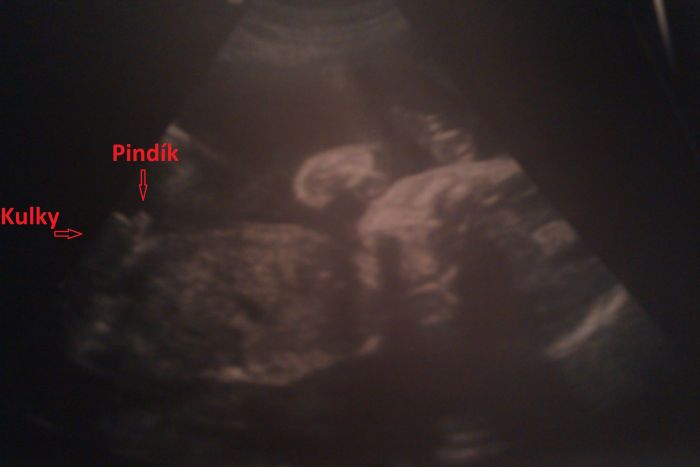

Pety já to mám stejné, obličej a záda sam pupínek, po saldkém se můžu utlouct a na ultrazvuku kulky

A ještě jedna fotečka, do obličeje vidět není, ale že je to kluk jak buk to nám předváděl celou dobu

[434926] Lenoraj, no tak to je úžasný fotečka, já to nikdy na těch ultrazvukách nepoznám, tak teď aspoň vím, co mám v pondělí s doktorkou hledat :-) Mooooooc pěkné, normálně mě to dojalo

[434929] Kozler mě to právě vždy doktor ukazuje a vysvětluje na co koukám a co kde je a já vždy vypadám jak retardovaná, jak jen čumím a blbě se usmívám

pak mě vždy dostane, jak tu fotku ukazuju tchýni a ona se mě ptá, co to je a vždy to vidí úplně jinak a mě se při tom zdá, že je to úplně jasné a několikrát ji tu fotku vysvětluju